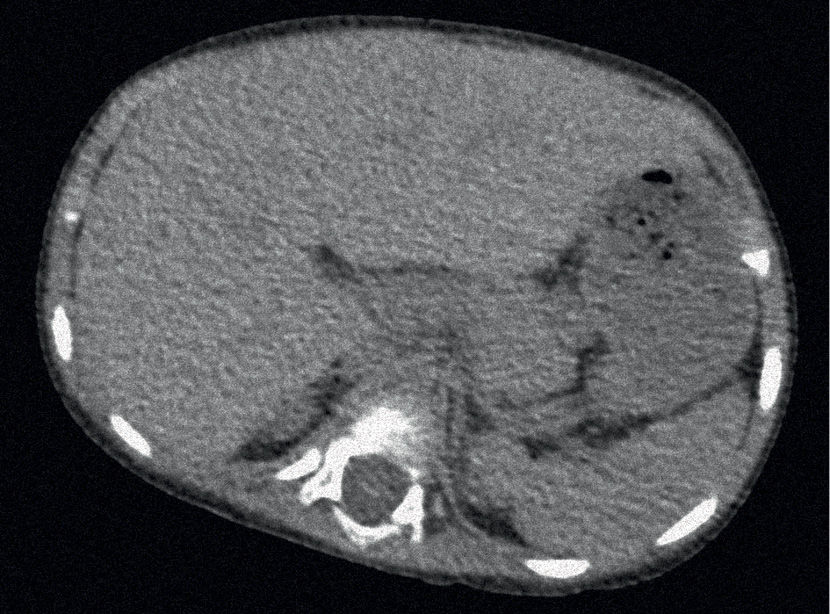

МРТ органов брюшной полости: нижний край правой доли печени заострен. Паренхима умеренно диффузно неоднородная, без признаков очаговых изменений. Селезенка умеренно увеличена, размером до 77 мм, контуры четкие, ровные, паренхима однородна. Поджелудочная железа визуализируется на всем протяжении, увеличена: головка до 19 мм, тело до 12 мм, хвост до 15 мм. Контуры неровные, паренхима однородная. На уровне сканирования определяется расширение просвета двенадцатиперстной кишки (19 мм), петель толстого кишечника (рис. 3).

Рис. 3. МРТ внутренних органов пациентки с НПСПА.